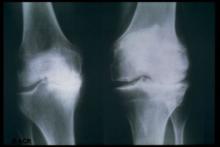

Why Would Hand OA Be Less Severe in Black People?

Osteoarthritis (OA) of the hand was less severe according to objective and pain-related markers in Black patients versus those of other racial/ethnic groups after adjustment for known risk factors, researchers found.

The finding was a major surprise and somewhat mysterious, insofar as previous studies have shown that OA of the hip and knee tended to be worse in Black people than in others. Indeed, it's unclear why race in and of itself would have any bearing on OA development.